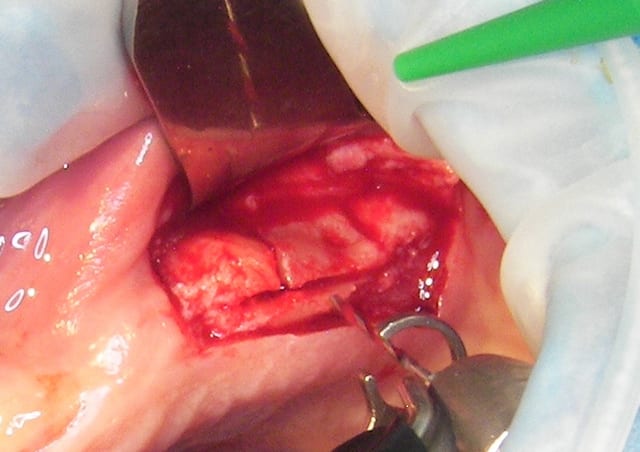

ou comme ça encore...

( agénésie de 12 - expansion osseuse sur une crête fine ) agénésie...

la suite à Sallanches les 2 et 3 Février pour ceux qui veulent encore s’inscrire)